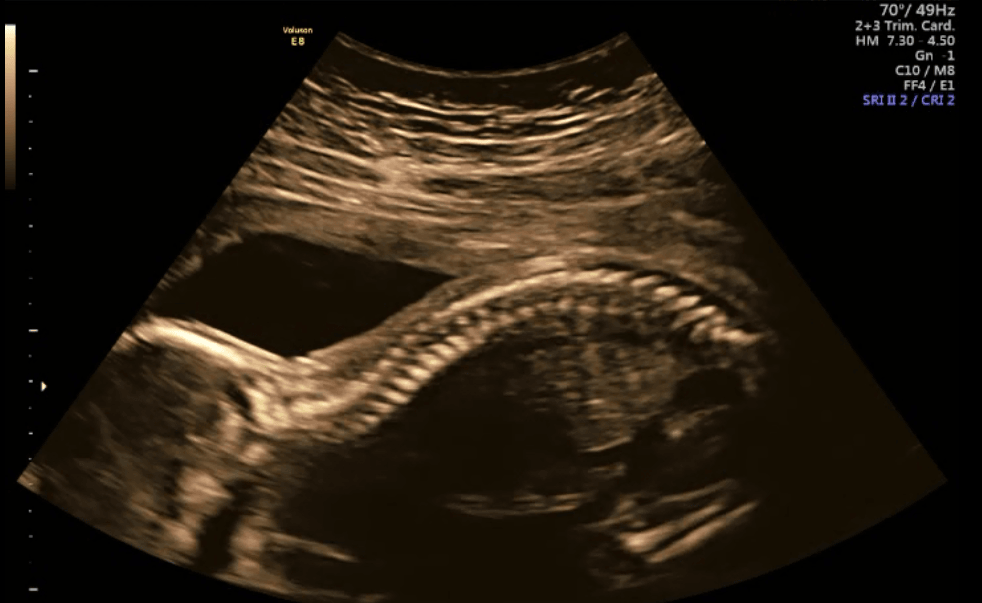

19+0 (wg usg i tego się teraz trzymamy!) wg OM 20+0

Waga : prawie 250 g i prawie 22 cm :biggrin2:

Tętno : 144(wczoraj), 150 (dzisiaj) :biggrin2:

Płeć : 100% chłopak :-) :)

Imię : Gabriel Mirosław :biggrin2:

Nosek - widoczny i śliczniutki (na prenatalnych podobno kośc nosowa była „nie do oceny”!)

Łożysko : na przedniej ścianie

Szyjka : 5 cm

Wszystkie narządy rozwijają się prawidłowo :-) :)

Termin porodu wg usg 20.04.2019 (jednak ze względu na cukrzycę typu2 nastąpi on 2 tygodnie wcześniej,ale konkretną datę poznam w późniejszym terminie) :-) :)